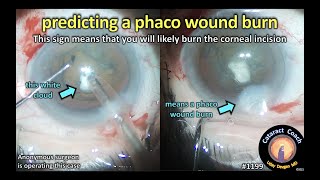

Case 1 Cataract Surgery Wound Burn CataractCoach 1199: predicting a phaco wound burn

CataractCoach 1199: predicting a phaco wound burn CataractCoach 1302: how to suture a phaco wound burn